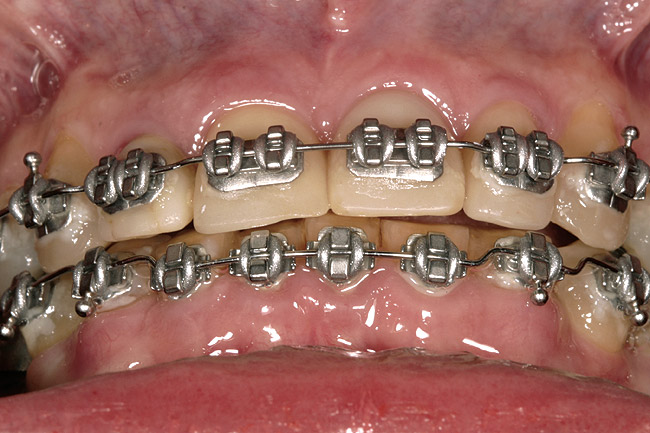

Figure 3  Orthodontics has intruded the incisors to create space to bond them to a pleasing length.

Figure 3

Again, the starting point is a set of mounted models, an orthodontic set-up, and a diagnostic wax-up. The worn teeth are cut from the set-up and waxed to normal length. They are then replaced in the set-up and become the guide for treatment. Whether they are lengthened before or during orthodontics depends upon whether space exists to lengthen them prior to orthodontics. If it does, they can be temporarily restored prior to treatment. If not, the orthodontist must first create space, then de-bracket the worn teeth and send the patient to the restorative dentist for temporary restoration. The brackets are then replaced and the orthodontics completed. The need to open space prior to correcting tooth length is common when utilizing orthodontics to intrude severely worn and over-erupted maxillary or mandibular incisors (Figure 2, Figure 3, Figure 4 and Figure 5).